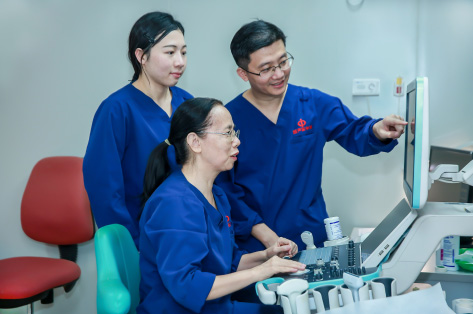

Estos son los problemas que el equipo de la profesora Xie Xiaoyan ha estado tratando de resolver. En este artĂculo, el equipo de la profesora Xie y el equipo de InvestigaciĂłn y Desarrollo de Mindray hacen un balance de la empresa conjunta: ?cĂłmo es la cooperaciĂłn entre el Departamento de EcografĂa y un socio de la industria? ?CĂłmo surgiĂł esta asociaciĂłn?

El Departamento de EcografĂa MĂ©dica de The First Affiliated Hospital de la Universidad Sun Yat-sen es un centro avanzado de diagnĂłstico y tratamiento ecogrĂĄficos en China que se dedica al tratamiento mĂ©dico, la investigaciĂłn y la educaciĂłn. La profesora Xie Xiaoyan, jefa del departamento y experta en ecografĂa abdominal y ecografĂa intervencionista, se ha dedicado a la investigaciĂłn sobre la ablaciĂłn de tumores durante muchos a?os.